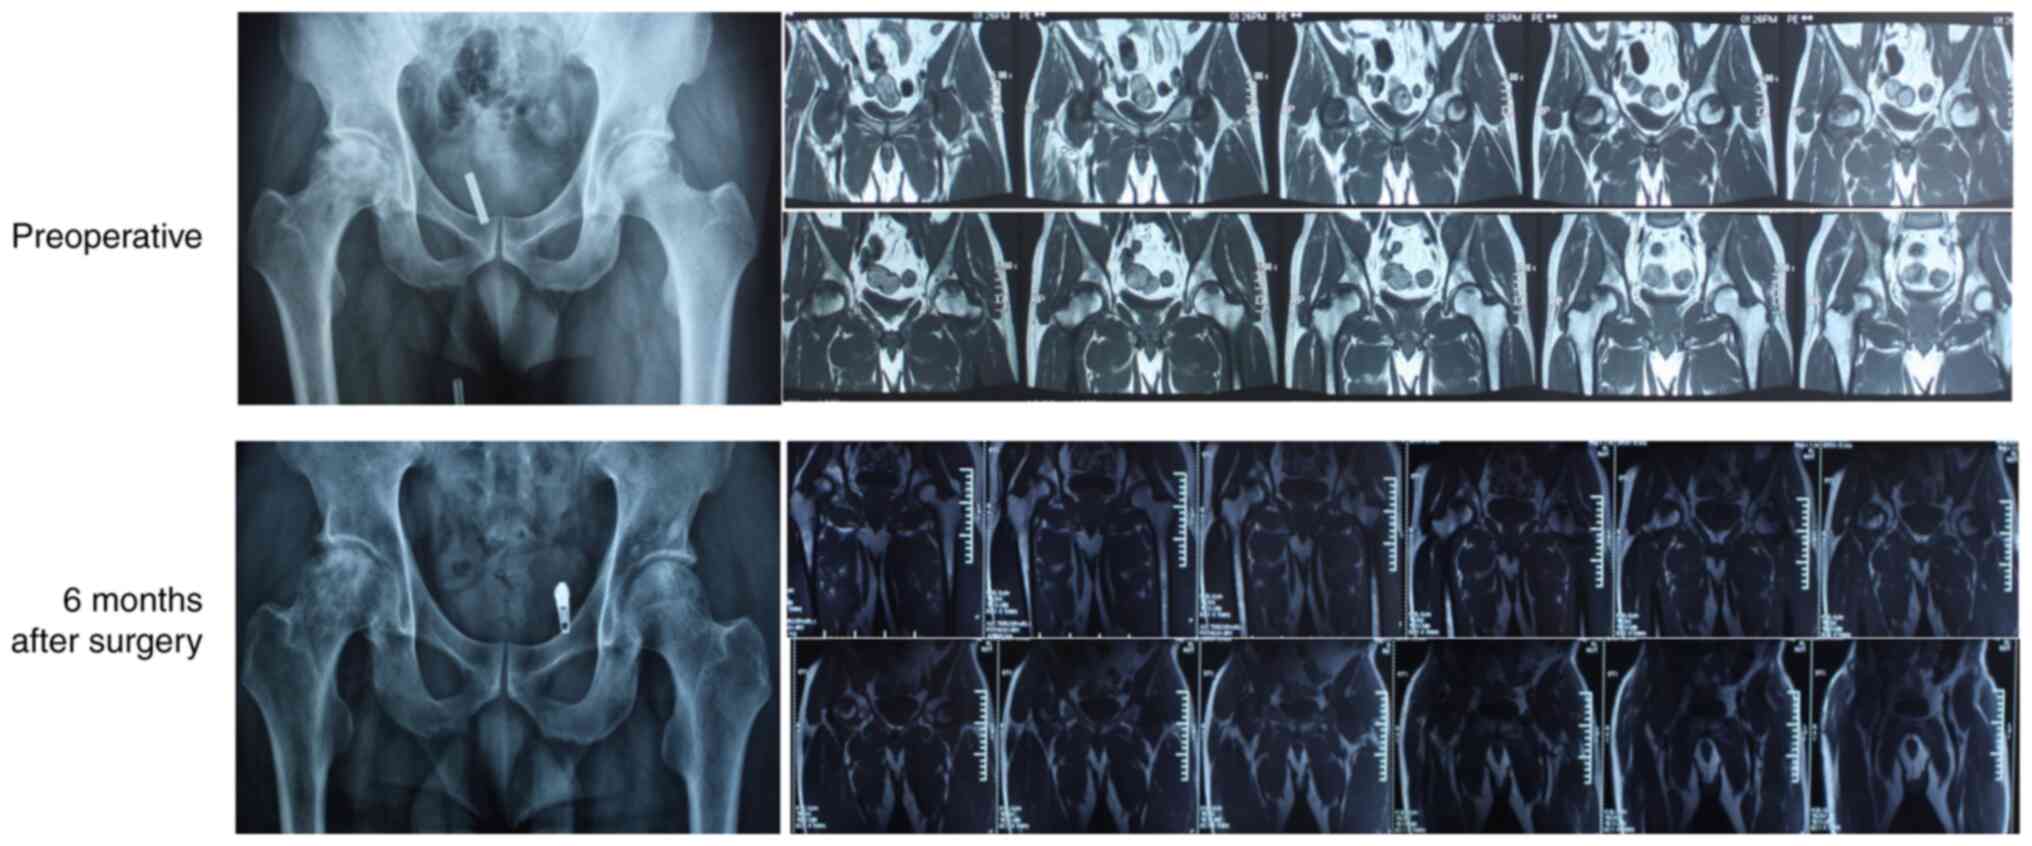

Previous studies (86,87) have shown that PRP can alleviate the symptoms of ONFH by the following mechanisms: i) Induction of angiogenesis and osteogenesis to promote bone healing, ii) inhibition of the inflammatory response in necrotic lesions, iii) prevention of GC-induced apoptosis and iv) activation of GC-induced osteogenesis and autophagy (87). While combination therapies incorporating PRP have achieved potent therapeutic effects (88), further prospective randomized clinical trials must be conducted to determine the optimal concentration of PRP and the proportion of stem cells (86). Platelet lysates can also treat femoral head necrosis by promoting the proliferation of osteoblasts and endothelial cells and reducing cell apoptosis and bone resorption (89). As shown in Fig. 3, CD combined with PRP therapy can accelerate the treatment of femoral head necrosis and promote healing of the decompression tunnel. Therefore, for patients with early-stage femoral head necrosis, a combination of PRP and CD is recommended.

Figure 3

Imaging results of patients with non-traumatic osteonecrosis of the femoral head 6 months after the combination treatment of core decompression and platelets in platelet-rich plasma.

Al-Mousawi et al (148) performed THA on 28 patients (35 hips) with ONFH secondary to sickle cell disease (SCD) and followed them up for an mean of 9.5 (5-15) years. One case developed infection and 6 cases developed aseptic loosening. SCD patients are at a higher risk during and post-THA. However, despite the higher failure rate in SCD patients, THA is still the most reliable option. As shown in Fig. 4, after 3 months of follow-up, THA led to significant recovery of ONFH.

Figure 4

Representative image of total hip arthroplasty on a non-traumatic osteonecrosis of the femoral head patient.